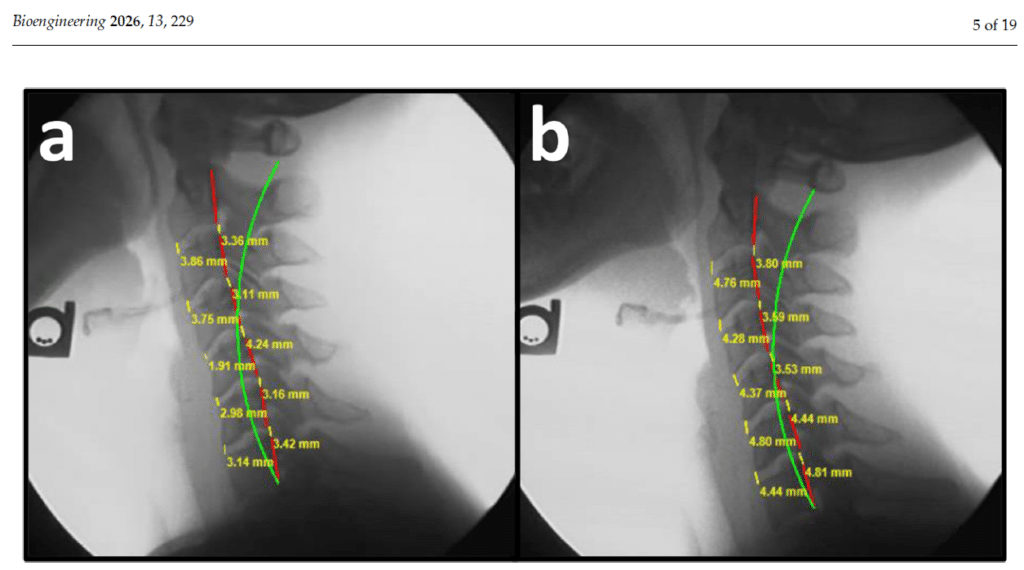

Diagnosis / Loss of Curve

Cervical Kyphosis After A Crash and Worse Outcomes.

Dear professionally integrated, Here is a paper where the authors look at multiple groups of patients and their prognosis after a car crash. These authors did publish that any sign…